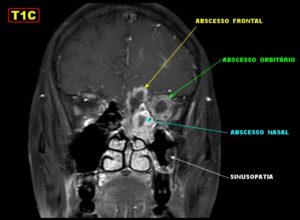

Нередко, особенно при хроническом течении, врачи прибегают к проведению компьютерной томографии. С ее помощью удается послойно оценить строение носа и придаточных его пазух. Главное преимущество этого метода – это возможность определить размер соустий, который влияет на частоту рецидивов заболевания и отражается на тактике лечения.

Единственными методами, которые наверняка могут определить сфеноидит, являются компьютерная томография (КТ) или магнитно-резонансная томография (МРТ) –

- информативнее других методов обнаруживают сфеноидит компьютерная или магнитно-резонансная томография;

КТ — исследование пазухи с помощью рентгеновского излучения. КТ позволяет выявить аномалии синуса, степень поражения слизистой. При исследовании с помощью КТ определяется уровень гноя в пазухе.

Ещё более информативным методом диагностики является МРТ — она выявляет послойные поражения, которые могут быть не замечены на КТ.